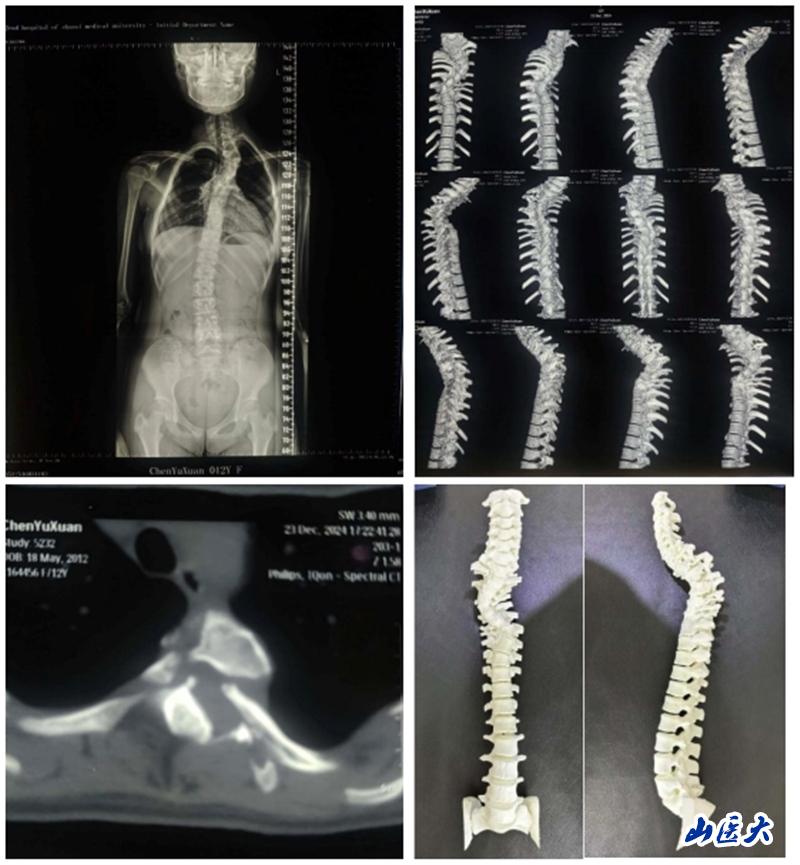

近日,我校第二醫院骨科脊柱畸形專業組成功為一名12歲少女解除了因神經纖維瘤病導致的脊柱側彎之苦。

這位小姑娘自幼便全身布滿咖啡斑,但因家庭貧困且對疾病認知不足,一直未進行詳細檢查。2024年7月,其祖母偶然發現孩子脊柱出現明顯畸形,遂展開多方求醫之路。在得知我校第二醫院骨科脊柱畸形專業組薛旭紅教授在脊柱側彎治療領域造詣頗深后,患者家屬慕名而來,前往我校第二醫院骨科門診就診。薛旭紅憑借深厚的醫學理論知識和豐富的臨床經驗,迅速診斷出患者為神經纖維瘤病所致的脊柱側彎,并立即安排其住院治療。進一步檢查發現,患者因神經纖維瘤病導致椎體骨破壞嚴重,椎弓根細。吖峭繁浼獠⑼谷胱倒苣冢質蹌訊群頭縵站。

面對如此復雜病情,薛旭紅教授與趙勝教授帶領團隊精心策劃,為患者量身定制了個性化的手術方案。2024年12月27日,在主治醫師董政權、麻醉醫師、器械護士王淑珍和巡回護士杜娟的通力協作下,骨科團隊成功完成了這場高難度、高風險的手術。